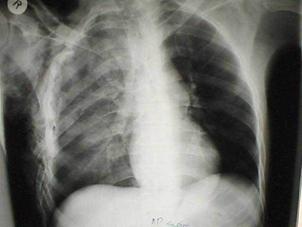

Traumatism toracic deschis Hemotorace stang masiv

Hemotorace stang masiv Hemotorace stang masiv

Hemotorace

drept masiv Hemotorace stang

Imagine CT Radiografie efectuata in ortostatism